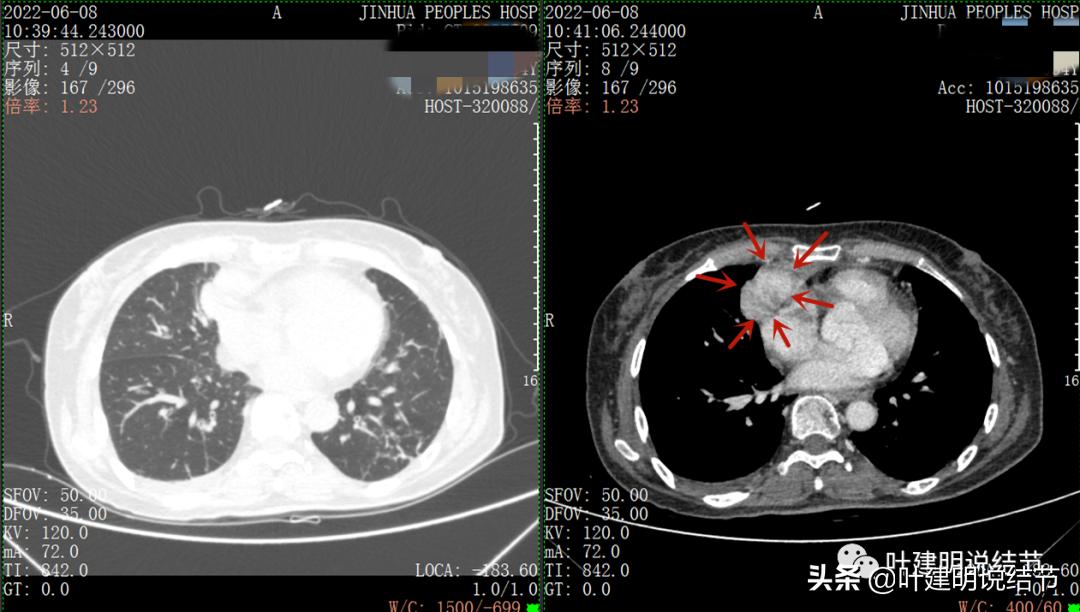

再来看看她的CT增强图像:

以下图片左侧是肺窗,右侧是纵隔窗。红色箭头示病灶,桔色箭头示无名静脉,黄色箭头示支气管,砖色箭头示上腔静脉,蓝色箭头示主动脉,紫色箭头示肺动脉。

病灶胸顶较高位置就出现了,在无名静脉水平

无名静脉略受压